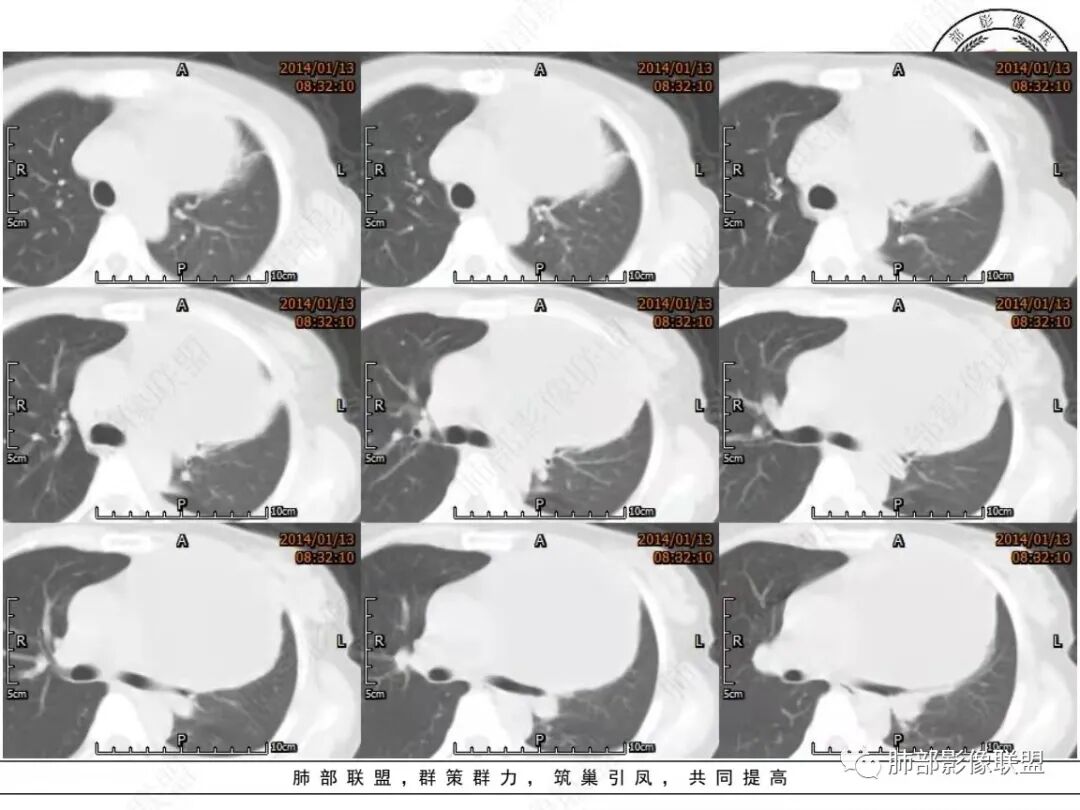

(1)畸胎瘤常见于血管前间隙。

(2)多呈囊性并可见脂肪、软组织,骨化或钙化等多种组织成分,囊性和脂肪成分是特征性的CT表现,但并非良性征象。 混合软组织密度结节部分含钙化或骨化成分也较具有诊断意义(所谓Rokitansky结节)。

(3)50%的病例可见钙化,病灶中牙齿和骨骼相对少见。

(4)囊性畸胎瘤(皮样囊肿)中有液体、脂肪,若有脂肪ー液体平面时更具有特征性、囊内液体的CT密度不一,有的可达软组织密度。

(5)肿瘤的囊性区由于密度低,被周围组织环绕,增强扫描时可见壁的环形强化。

(6)皮样囊肿的囊壁多较清晰,厚度一般为2-5mm。